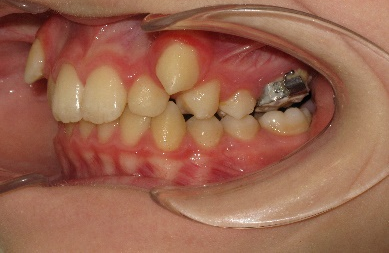

На завершении проведения этапа нивелирования начинается активная дистализация первых и вторых премоляров на верхней челюсти с помощью открывающих пружин, выполненных из сплава NiTi c незначительной силовой нагрузкой. (рис.7.)

Рис.7. Этап нивелирования на аппарате NexStep Pro 0.22

После дистализации боковых сегментов на верхней челюсти и правильной постановки клыков в зубной ряд проведена фиксация аппарата на нижний зубной ряд и дальнейшая коррекция окклюзии проводится по стандартному протоколу, т.е. нормализация формы зубных рядов на верхней и нижней челюсти с правильной постановкой зубов по торку в боковых и во фронтальном отделах, что дает реализация программы, заложенная в пассивной самолигирующей брекет- системе NexStep Pro 0.22. (рис.8)

Рис.8. Этап контроля торка на верхней челюсти и фиксация аппарата на нижней челюсти для проведения этапа нивелирования.